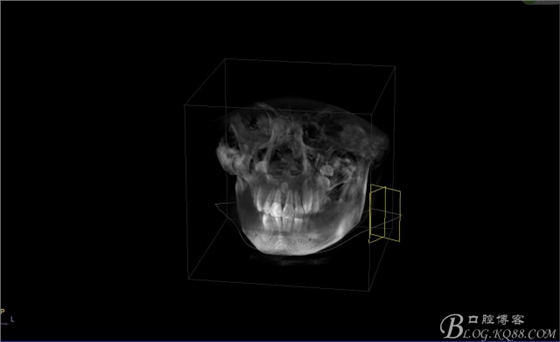

圖4.三維重建影像:12根尖區(qū)的多生牙位置更高。手術(shù)難度大